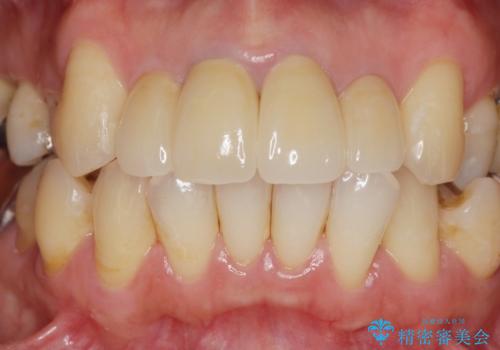

歯ぐきの位置は経年的に変化することがあります。その際にもジルコニアクラウンはクラウンの際が黒くなく目立ちにくく審美的なクラウンと言えます。

劣化したクラウンを除去し、再発した虫歯を徹底的に除去したのち根管治療・ファイバーコア築盛を行いジルコニアクラウン製作へと移ります。

- 52万円(仮歯・ファイバーコア・ジルコニアクラウン×4)費用は治療当時の料金となります